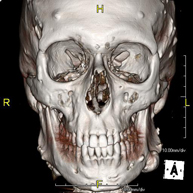

- TC Macizo facial

Prueba radiológica que consiste en obtener imágenes del macizo facial (cara) de alta definición anatómica mediante el empleo de un equipo de TC (Tomografía Computarizada). Indicaciones: tumores, cirugía plástica.